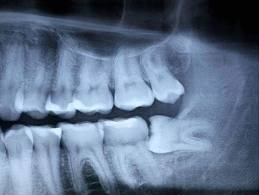

Vađenje neizniklih zuba (vađenje impaktiranih zuba) jedna je od najčešćih intervencija. Od svih neizniklih zuba najveći procenat odlazi na umnjake koji svojim rastom ili položajem ugrožavaju okolne zube i strukture.